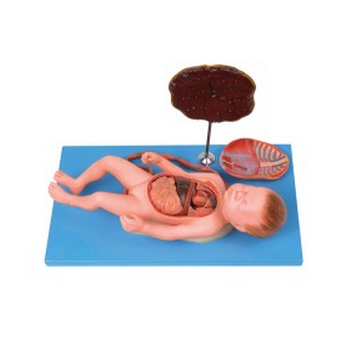

GD/A42008胎盤臍帶與胎兒附內臟模型產品介紹:1、該模型由足月胎兒、胸腹部內臟器官、胎盤、臍帶等13個部件組成。顯示胎兒整體結構,共有50個部位指示標志。2、尺寸:高43.5cm,寬16.5cm...